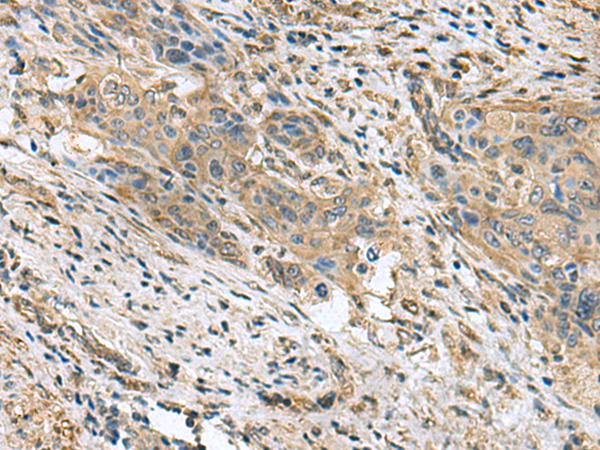

分类: 科研抗体货号: P10200别名: SK2; BCYM4; ATPSK2应用: IHC反应种属: Human, Mouse